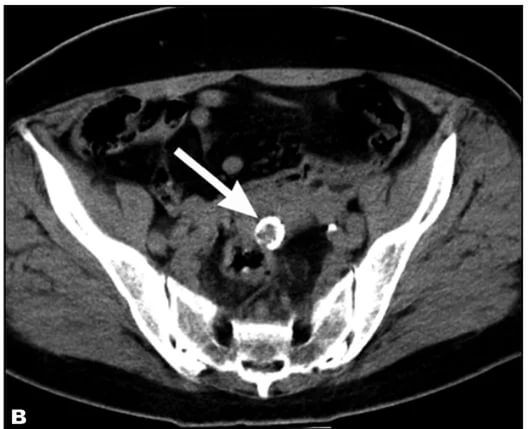

| Диагностика | УЗИ, КТ, МРТ. | Визуализация кальцификатов в миоме на изображениях. |

Для диагностики данного типа новообразований используются те же методы, что и для обычных опухолей. Тем не менее, ультразвуковое исследование может столкнуться с определенными трудностями. Кальцинированные опухоли иногда сложно идентифицировать на УЗИ, особенно если они небольшие.

Более четкие результаты можно получить только при наличии узлов диаметром от 8 мм, так как они кальцинируются довольно редко. Обычно наличие таких новообразований на УЗИ определяется по гиперэхогенным включениям с акустическим эффектом.

Магнитно-резонансная томография (МРТ) обладает большей точностью и информативностью. Стоимость МРТ матки составляет около 3000 рублей, что делает этот метод довольно дорогим. Однако в некоторых случаях это единственный способ для установления точного диагноза. МРТ является наиболее информативным методом, который практически исключает вероятность ошибки. Он позволяет точно определить расположение миом, их размеры, а также выяснить, могут ли они быть кальцинированными.

Диагностика кальцинированной миомы обычно включает ультразвуковое исследование (УЗИ), которое позволяет визуализировать миоматозные узлы и их кальцификацию. В некоторых случаях может потребоваться магнитно-резонансная томография (МРТ) для более детального изучения состояния матки. Врач также может провести гинекологический осмотр и собрать анамнез для определения возможных симптомов и факторов риска.